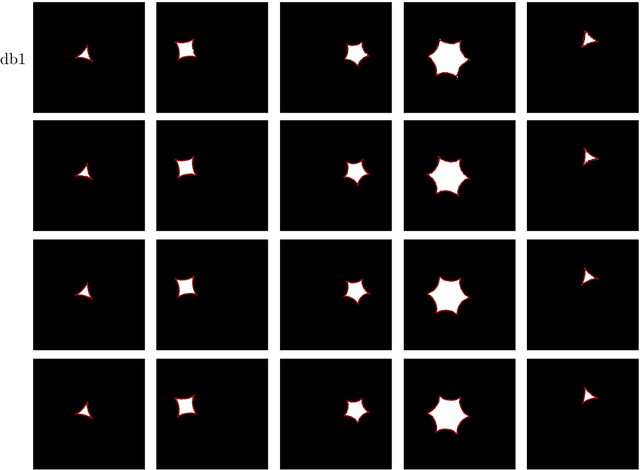

Abstract:We propose a novel deep learning framework for fast prediction of boundaries of two-dimensional simply connected domains using wavelets and Multi Resolution Analysis (MRA). The boundaries are modelled as (piecewise) smooth closed curves using wavelets and the so-called Pyramid Algorithm. Our network architecture is a hybrid analog of the U-Net, where the down-sampling path is a two-dimensional encoder with learnable filters, and the upsampling path is a one-dimensional decoder, which builds curves up from low to high resolution levels. Any wavelet basis induced by a MRA can be used. This flexibility allows for incorporation of priors on the smoothness of curves. The effectiveness of the proposed method is demonstrated by delineating boundaries of simply connected domains (organs) in medical images using Debauches wavelets and comparing performance with a U-Net baseline. Our model demonstrates up to 5x faster inference speed compared to the U-Net, while maintaining similar performance in terms of Dice score and Hausdorff distance.